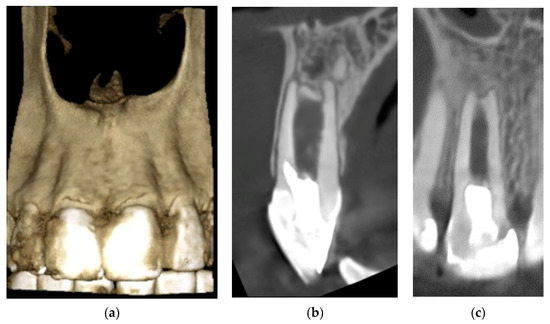

2. Detailed Case Description